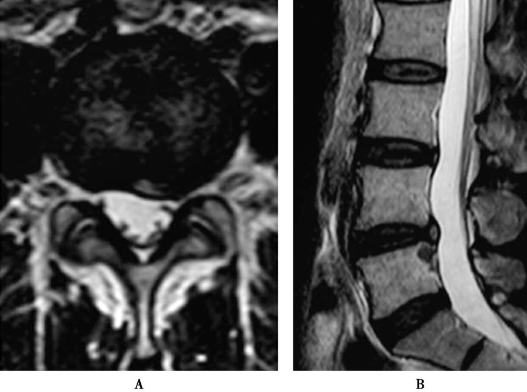

CT显示L4/5节段的椎间盘突出脱垂型(图1)。MRI示L4/5节段的椎间盘突出到Ⅲ层面(图2)。红外热成像显示左侧下肢的皮温明显低于右侧(图3)。

图2 MRI L4~5节段矢状位片:椎间盘脱垂到Ⅲ层面

图31 术后1周复查MRI L4/5A.轴位;B.矢状位